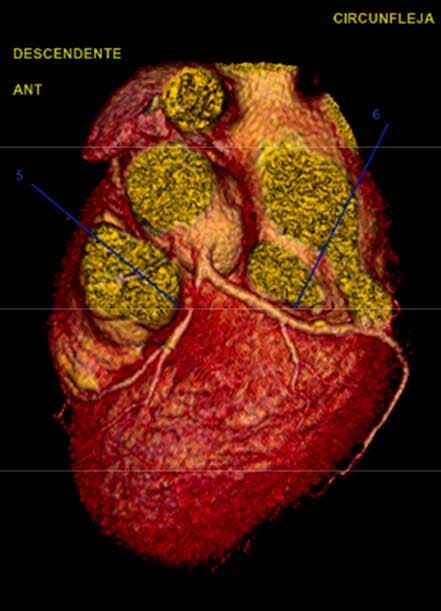

- Angiotomografía coronaria

- Imagen cardiovascular

- Enfermedades de las arterias coronarias o coronariopatía